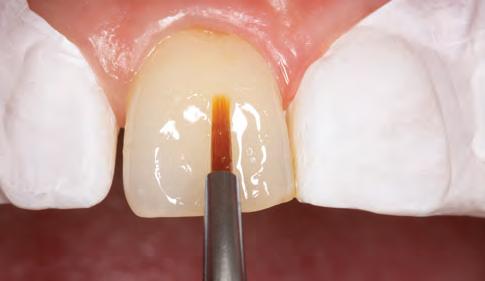

Injectable technique matrices: One method that offers a fast and easy solution to predictably converting a diagnostic wax-up into composite restorations is made possible by the injectable technique, using transparent silicone matrices and flowable resin composites.12 (Fig. 6)

This technique significantly reduces the sensitivity of the procedure and the time spent in the chair, delivering accurate and reliable outcomes, particularly when integrated with a digital workflow.14,22

With this approach, a wax-up is created, and an impression using a clear PVS material is obtained.12, 22 Access holes are made through the clear PVS index at the incisal edges to insert the tip of a flowable material to copy and transfer the anatomy created by the wax-up.22 The PVS index is tried in intra-orally to verify fit.12 The teeth adjacent to the tooth to be restored are covered with polytetrafluoroethylene tape. The tooth to be restored is etched and bonded.33 The index is inserted. The flowable composite is injected through the access holes, thus replicating the contours created from the wax-up. The remaining teeth are to be restored, so repeat this procedure. Once the index has been removed, the final restorations are polished and completed.8

While flow composite restorations may remain more prone to wear or fracture, they can be readily repaired, prolonging the restoration’s lifespan.34 These restorations are nevertheless regarded as contraindicated for stress-bearing areas.8,22, 35

Fig. 6a: Patient requested to build peg laterals to fill the spaces between her teeth.

Fig. 6b: Clear PVS index try-in.

Fig. 6c: Injection of flowable composite.

Fig. 6d: Post-operative result.